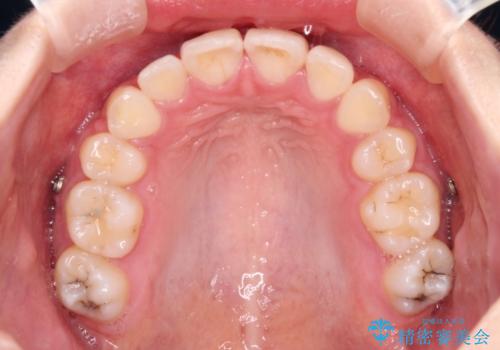

- 地元で抜歯治療を行っている途中、東京へ転職したため治療を継続して欲しいとのことで来院された患者様です。

出っ歯を抜歯矯正にて治療をしていらっしゃいましたが、抜歯スペースが少し残っていたため、閉じて歯列を仕上げていくこととしました。